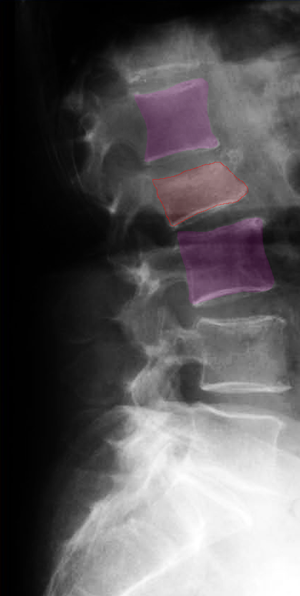

Η σπονδυλοπλαστική είναι μια ελάχιστα επεμβατική χειρουργική μέθοδος με την οποία γίνεται ανάταξη του κατάγματος ενός (ή περισσοτέρων) θωρακικών ή οσφυϊκών σπονδύλων και κυρίως ενίσχυση αυτών μέσω της διαδερμικής έγχυσης ακρυλικού πολυμερούς στο σώμα του σπονδύλου. Στην κυφοπλαστική, της έγχυσης του πολυμερούς προηγείται η τοποθέτηση και διαστολή εμφυτεύματος έτσι ώστε να επιτευχθεί δραστικότερη ανάταξη του κατάγματος πριν εγχυθεί το υλικό. Οι επεμβάσεις αυτές έχουν ως συνηθέστερη ένδειξη τα οστεοπορωτικά κατάγματα της σπονδυλικής στήλης και σπανιότερα, υπό προϋποθέσεις και σε πολύ επιλεγμένους ασθενείς, τους τραυματισμούς και τους όγκους των σωμάτων των σπονδύλων της θωρακικής και οσφυϊκής μοίρας της σπονδυλικής στήλης. Πραγματοποιούνται συνήθως διαδερμικά με την βοήθεια ειδικού συστήματος βελόνης για την προσπέλαση και έγχυση του πολυμερούς και υπό ακτινοσκοπικό έλεγχο. Η σπονδυλοπλαστική απαιτεί κατά κανόνα μόνο τοπική αναισθησία ενώ η κυφοπλαστική γενική. |

Η συνηθέστερη ένδειξη της σπονδυλοπλαστικής και της κυφοπλαστικής είναι τα οστεοπορωτικά κατάγματα της θωρακικής και οσφυϊκής μοίρας της σπονδυλικής στήλης. Η σπονδυλοπλαστική πραγματοποιείται σε αυτούς τους ασθενείς με προοπτική να αποφευχθεί περαιτέρω καθίζηση ή κυφωτική παραμόρφωση του σπονδύλου, τις οποίες μπορεί και να ανατάξει μερικώς, και έχει εξαίρετο αναλγητικό αποτέλεσμα. Η κυφοπλαστική προσφέρει επιπλέον των ανωτέρω και δραστικότερη ανάταξη των ανατομικών παραμορφώσεων του σπονδύλου. Οι μέθοδοι μπορούν να εφαρμοστούν, υπό προϋποθέσεις και σε αυστηρά επιλεγμένους ασθενείς, σε ορισμένες τραυματικές κακώσεις όπως και σε όγκους του σώματος των σπονδύλων.

Σπονδυλοπλαστική οσφυϊκού σπονδύλου. |